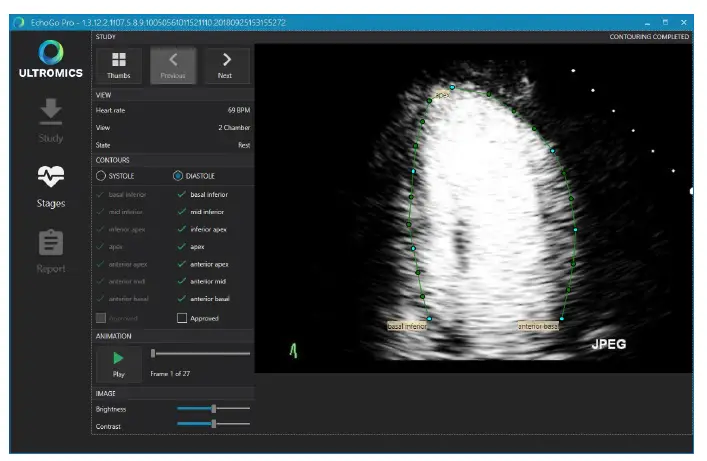

If a batch of received files pass the technical QC, the algorithm for automated contour detection of the endocardium of the LV (ROI’s) is applied. The auto-contouring is detected at end-systole (ES) and end-diastole (ED) for the apical two chamber (A2C), four-chamber (A4C) and mid-ventricular SAX views at both rest and peak stages. Appendix A provides examples of contours that shall be rejected and accepted.

Figure 1: Example of the Thumbnail screen displaying the different stages and views

Figure 2: Example of the contouring screen used to access the quality of the generated auto-contours